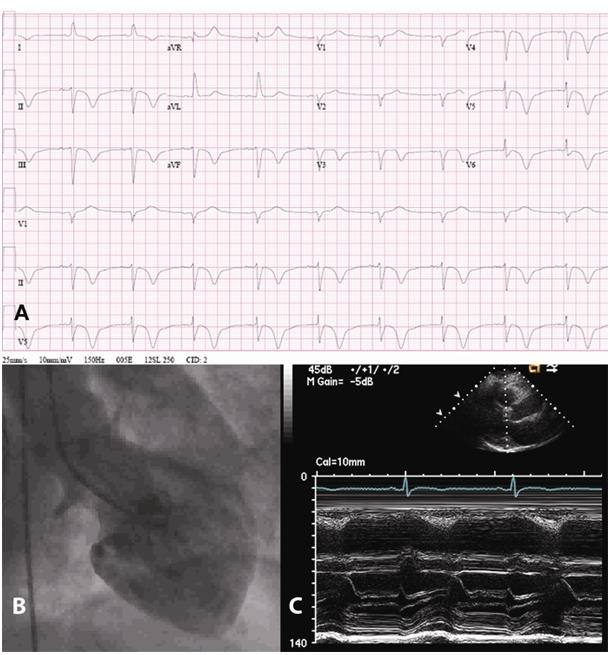

E sembra infarto anche ai medici: un esame del sangue che rileva un aumento degli enzimi di necrosi del muscolo cardiaco e l’elettrocardiogramma che presenta un tracciato alterato. ‘Ma la prova del nove che non e’ infarto – dice Francesco Bovenzi, direttore del Dipartimento Cardio-respiratorio dell’ ospedale Campo di Marte di Lucca – arriva con l’angiografia, che risulta negativa. Se le coronarie sono sane e non ci sono trombi ne’ placche, non ci sono dubbi: e’ sindrome di Tako-Tsubo’, cosi’ chiamata dai giapponesi che l’hanno per la prima volta descritta, per la forma che assume il cuore. Il meccanismo del disturbo e’ poco conosciuto. ‘A Lucca – aggiunge Bovenzi – stiamo valutando il nesso causale dell’ intrigante correlazione tra mente e corpo, per l’ evidenza che il disturbo sia scatenato da un intenso stress emozionale nel 33-45% dei casi o fisico nel 17-22% dei soggetti’. L’ipotesi e’ che il sistema nervoso simpatico, che risponde al comando ‘scappa e fuggi’, responsabile di accelerare per esempio i battiti del cuore, gli atti respiratori, le contrazioni del nostro intestino, vada in tilt perche’ si e’ stressati, depressi o ansiosi. Il suo superlavoro fa produrre sostanze pro-infiammatorie, che restringono il lume dei vasi sanguigni, producono i micidiali radicali liberi e provocano un danno forse anche cellulare, sebbene momentaneo, al cuore’. La cura si avvale di terapie ansiolitiche e di supporto al cuore. Di solito il muscolo cardiaco in pochi giorni recupera le sue energie e ritorna a pompare con forza il sangue.